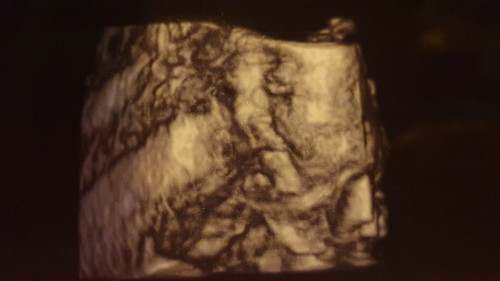

31W 1D

แอบดูสาวน้อย 31 สัปดาห์ อารมณ์ดียิ้มเก่ง น้ำหนัก 1,609 กรัม แล้วค่ะ